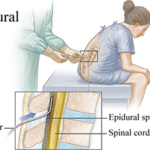

Top 7 Mindful Techniques for Painless Vaginal Delivery

Author: Dr. Tejinder Kaur MBBS, Diploma in Hospital Administration, Diploma of National Board training, Fellowship in Reproductive MedicineConsultant: Obstetrician & Gynaecologist at Motherhood Hospital, Mohali Anticipating the arrival of a baby is remarkable for women. A woman goes through various physical, psychological, and hormonal changes to prepare for labour. According to Dr Tejinder Kaur, MBBS, […]